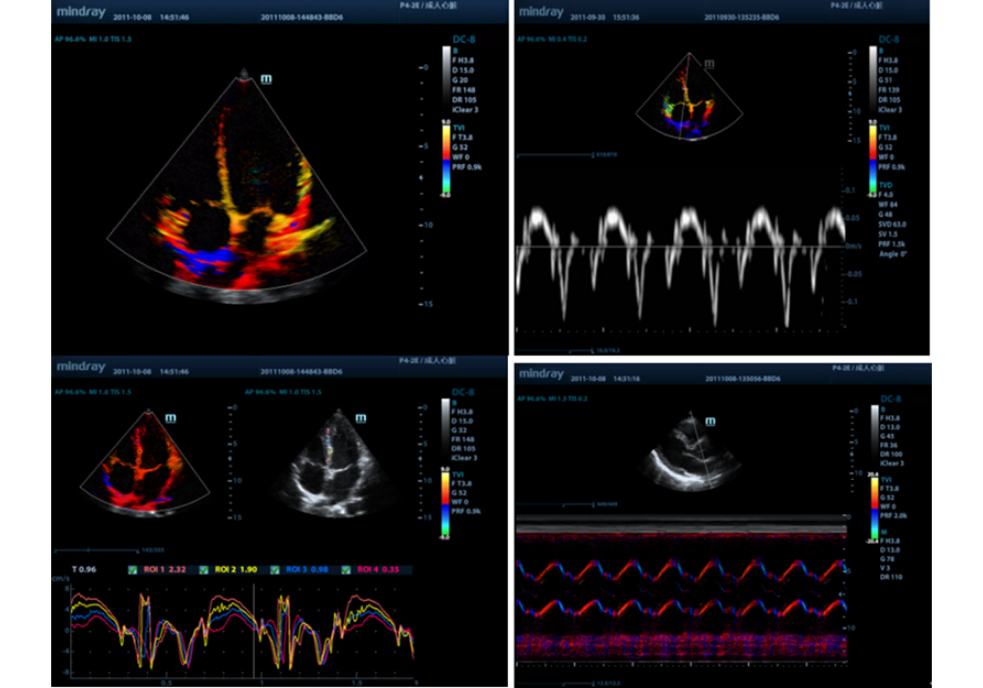

TDI

Tissue Doppler Imaging allows you to quantitatively evaluate local myocardial movement and function, providing complete TDI modes for faster and direct diagnoses.